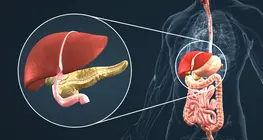

Certain liver diseases (hepatitis, cirrhosis) and their management.

Hormones secreted by the pancreas.

Understanding gallbladder and pancreatic disorders: treatment and management.